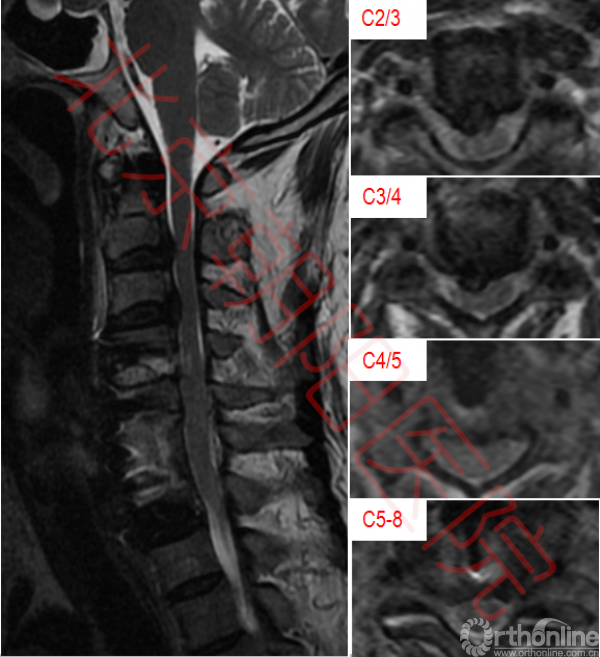

颈椎核磁如图:可见多节段脊髓压迫。

图2:如图可见脊髓多节段受压,C6、C7椎体及椎间盘高信号,C6-C7椎体后方可见高密度影,C5-C8椎体前方高密度影。脊髓内可见高信号区域

经过数次讨论,决定手术干预。手术以清创减压为主,尽可能清除由脓肿导致的脊髓受压。由于C6、C7椎体破坏严重,行C6椎体全切、C7椎体部分切除;术前核磁可见C2/3、C3/4、C4/5间盘突出,脊髓受压明显,以C4/5节段压迫最重,综合考虑,决定仅切除C4/5间盘解除脊髓压迫;取髂骨植骨、钛板内固定重建颈椎稳定性。术中切除椎体及椎间盘送病理及病原学培养。